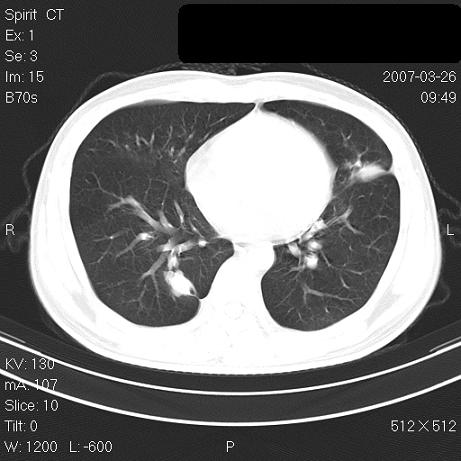

标题: CT7171B:补充治疗后2周复查 [打印本页]

标题: CT7171B:补充治疗后2周复查

治疗后2周复查,请讨论

结合以前的ct片,还是考虑肺挫伤,吸收多了。

支持:创伤性湿肺。现肺挫裂伤(出血 积气)大部分吸收。建议继续治疗!

结合以前的ct片,支持创伤性湿肺。现大部分吸收。

支持:创伤性湿肺、肺挫裂伤。现肺挫裂伤(出血、渗出、液气腔)大部分吸收。建议继续治疗!

支持:创伤性湿肺、肺挫裂伤。现肺挫裂伤(出血、渗出、液气腔)大部分吸收.

结合老片支持创伤性湿肺、肺挫裂伤。

经治疗后病灶明显吸收,考虑创伤性湿肺、肺挫裂伤